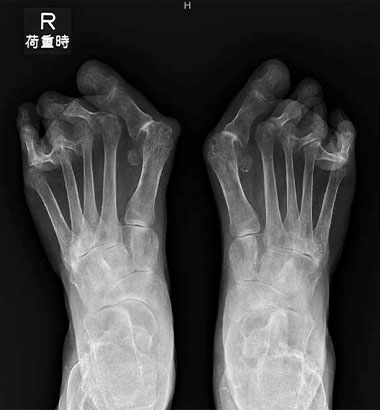

TMT関節固定術 (Lapidas変法):

あしのおやゆびの根元の関節(第1足根中足関節:TMT関節)の表面の軟骨を削り、骨の長さと位置を矯正し、関節間をプレート固定する方法です。

MTP関節固定術:

あしのおやゆびの関節(MTP関節)の軟骨を削り、おやゆびをまっすぐな位置に戻した状態で、プレート固定する方法です。

術前

術後